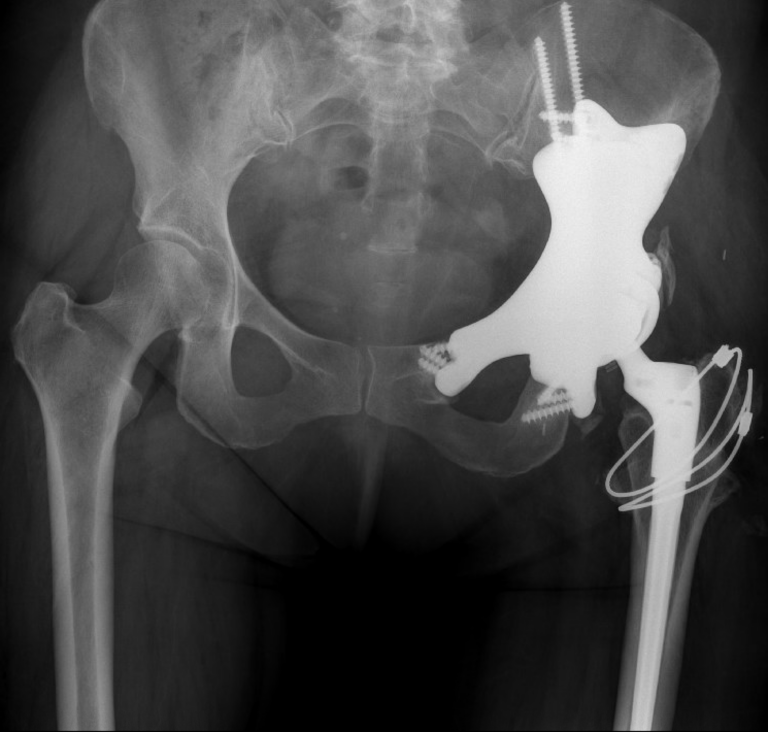

As family tried to reassure her everything would be okay, Tracy and her husband, Jason, met with the orthopaedic oncology team at The Ottawa Hospital and confirmed Tracy’s fears. “Tracy had chondrosarcoma, a malignant bone tumour of the pelvis and it also involved the hip joint. These tumours can spread and metastasize — they’re dangerous tumours,” explains Dr. Joel Werier, Head of The Ottawa Hospital Sarcoma Program and orthopaedic oncologist.

Dr. Werier explained to Tracy that surgery was her only option for this type of cancer. “It’s very important that we remove the full tumour, but the challenge is it meant removing a good portion of the pelvis and the hip joint, so mobility becomes an issue.”

However, thanks to medical advancements, The Ottawa Hospital can offer some patients a new option for bone reconstruction — a 3D customized pelvic implant.

The 3D pelvic implant is custom designed based on MRIs, CT scans, and other imaging. It is silver coated to reduce the risk of infection — a risk associated with this option.

Complex orthopaedic surgery planned

The 16-hour operation was set for February 2024, and once the tumour was removed, the surgical team placed the implant. “The design comes with guides to make sure the prothesis fits, and Tracy’s fit perfectly to her bone. It recreated the pelvis that was removed, and you have a hip replacement, as opposed to an empty hip,” explains Dr. Werier.

The implant is made with a porous type of metal, which over the course of 12+ months allows the surrounding bone to grow into the implant, giving the patient a solid pelvis.